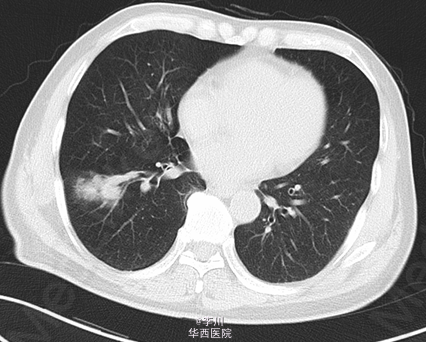

患者男,73岁,因“咳痰伴痰中带血2+月”入院。患者于2+月前无明显诱因出现咳痰伴痰中带血,无咳嗽、胸闷、胸痛等症状,未予以处理。10+天前于外院就诊,行胸部CT、心脏超声、纤支镜等检查示:右肺占位。予以口服及输液治疗13天(具体不详),症状无明显好转。

于全麻下行“VATS右肺下叶切除术+淋巴结清扫术”,术中见:肿块块位于右肺下叶,约4.2*3.9cm大小,脏层胸膜皱缩、无侵犯壁层胸膜;术中冰冻结果:(右下肺肿块)腺癌。

肺癌的分叶征是周围型小肺癌最常见的基本征象。其病理基础一是与肿瘤边缘各部位肿瘤细胞分化程度不一,生长速度不同有关;二是肺的结缔组织间隔,进入肿瘤的血管、支气管分支、从肿瘤内向外生长的血管和结缔组织等引起肿瘤生长受限并产生凹陷,从而形成分叶的形态。分叶征对于鉴别肺部包块良恶性具有重要价值。